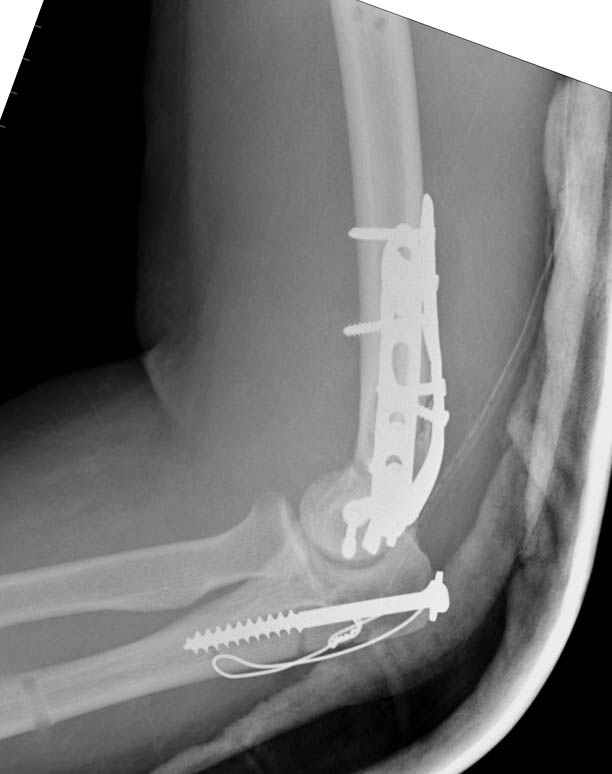

Солидарен с мнением обоих Александров (Челнокова и Рыкова): точную репозицию такого перелома вряд ли удастся выполнить закрыто. Даже во время открытого вмешательства это сделать непросто. Неслучайно предложен костно-пластический доступ с временным отсечением локтевого отростка. И по методу фиксации согласен с Александром Челноковым: 2 пластины. В качестве примера привожу рентгенограммы одного из наших пациентов с аналогичным повреждением.

С уважением, А. Золотов, Приморский край.